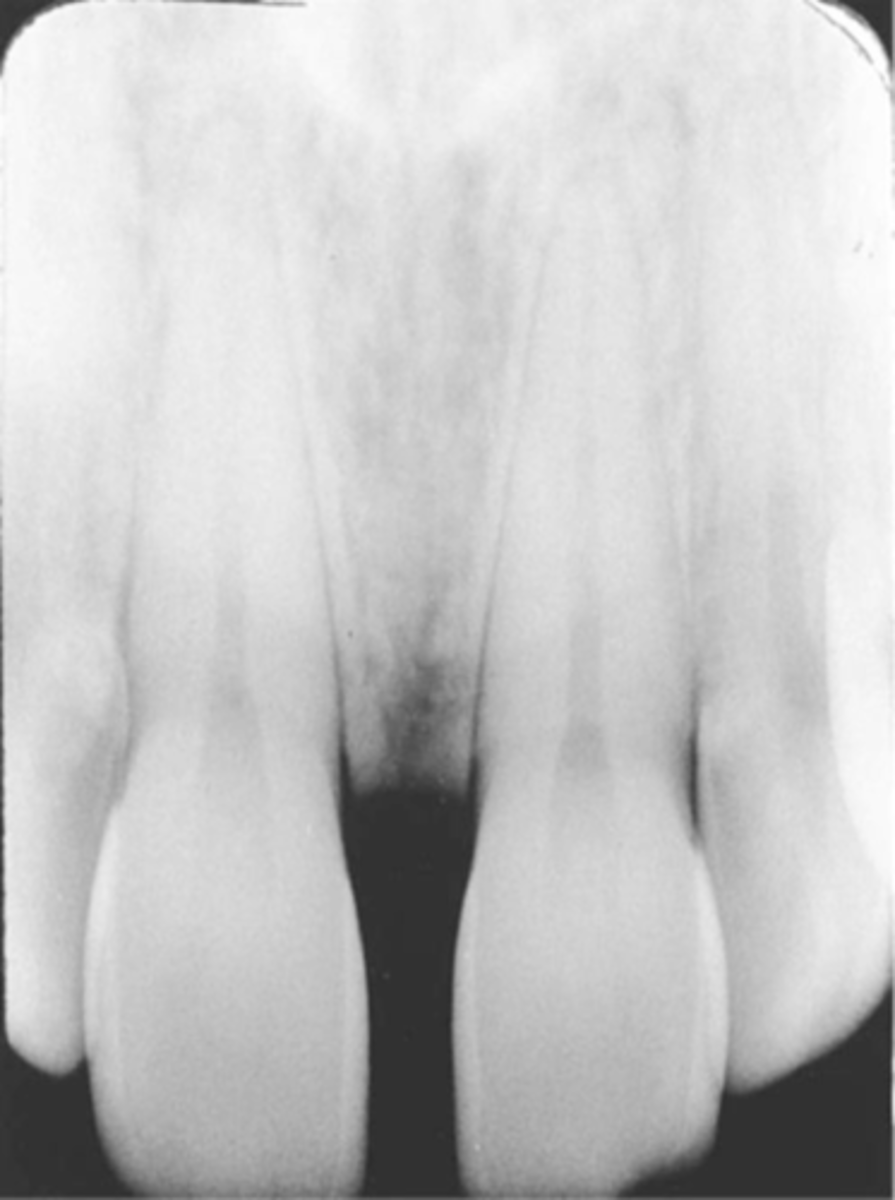

Elongated images

Long distorted teeth. Too little vertical angulation.